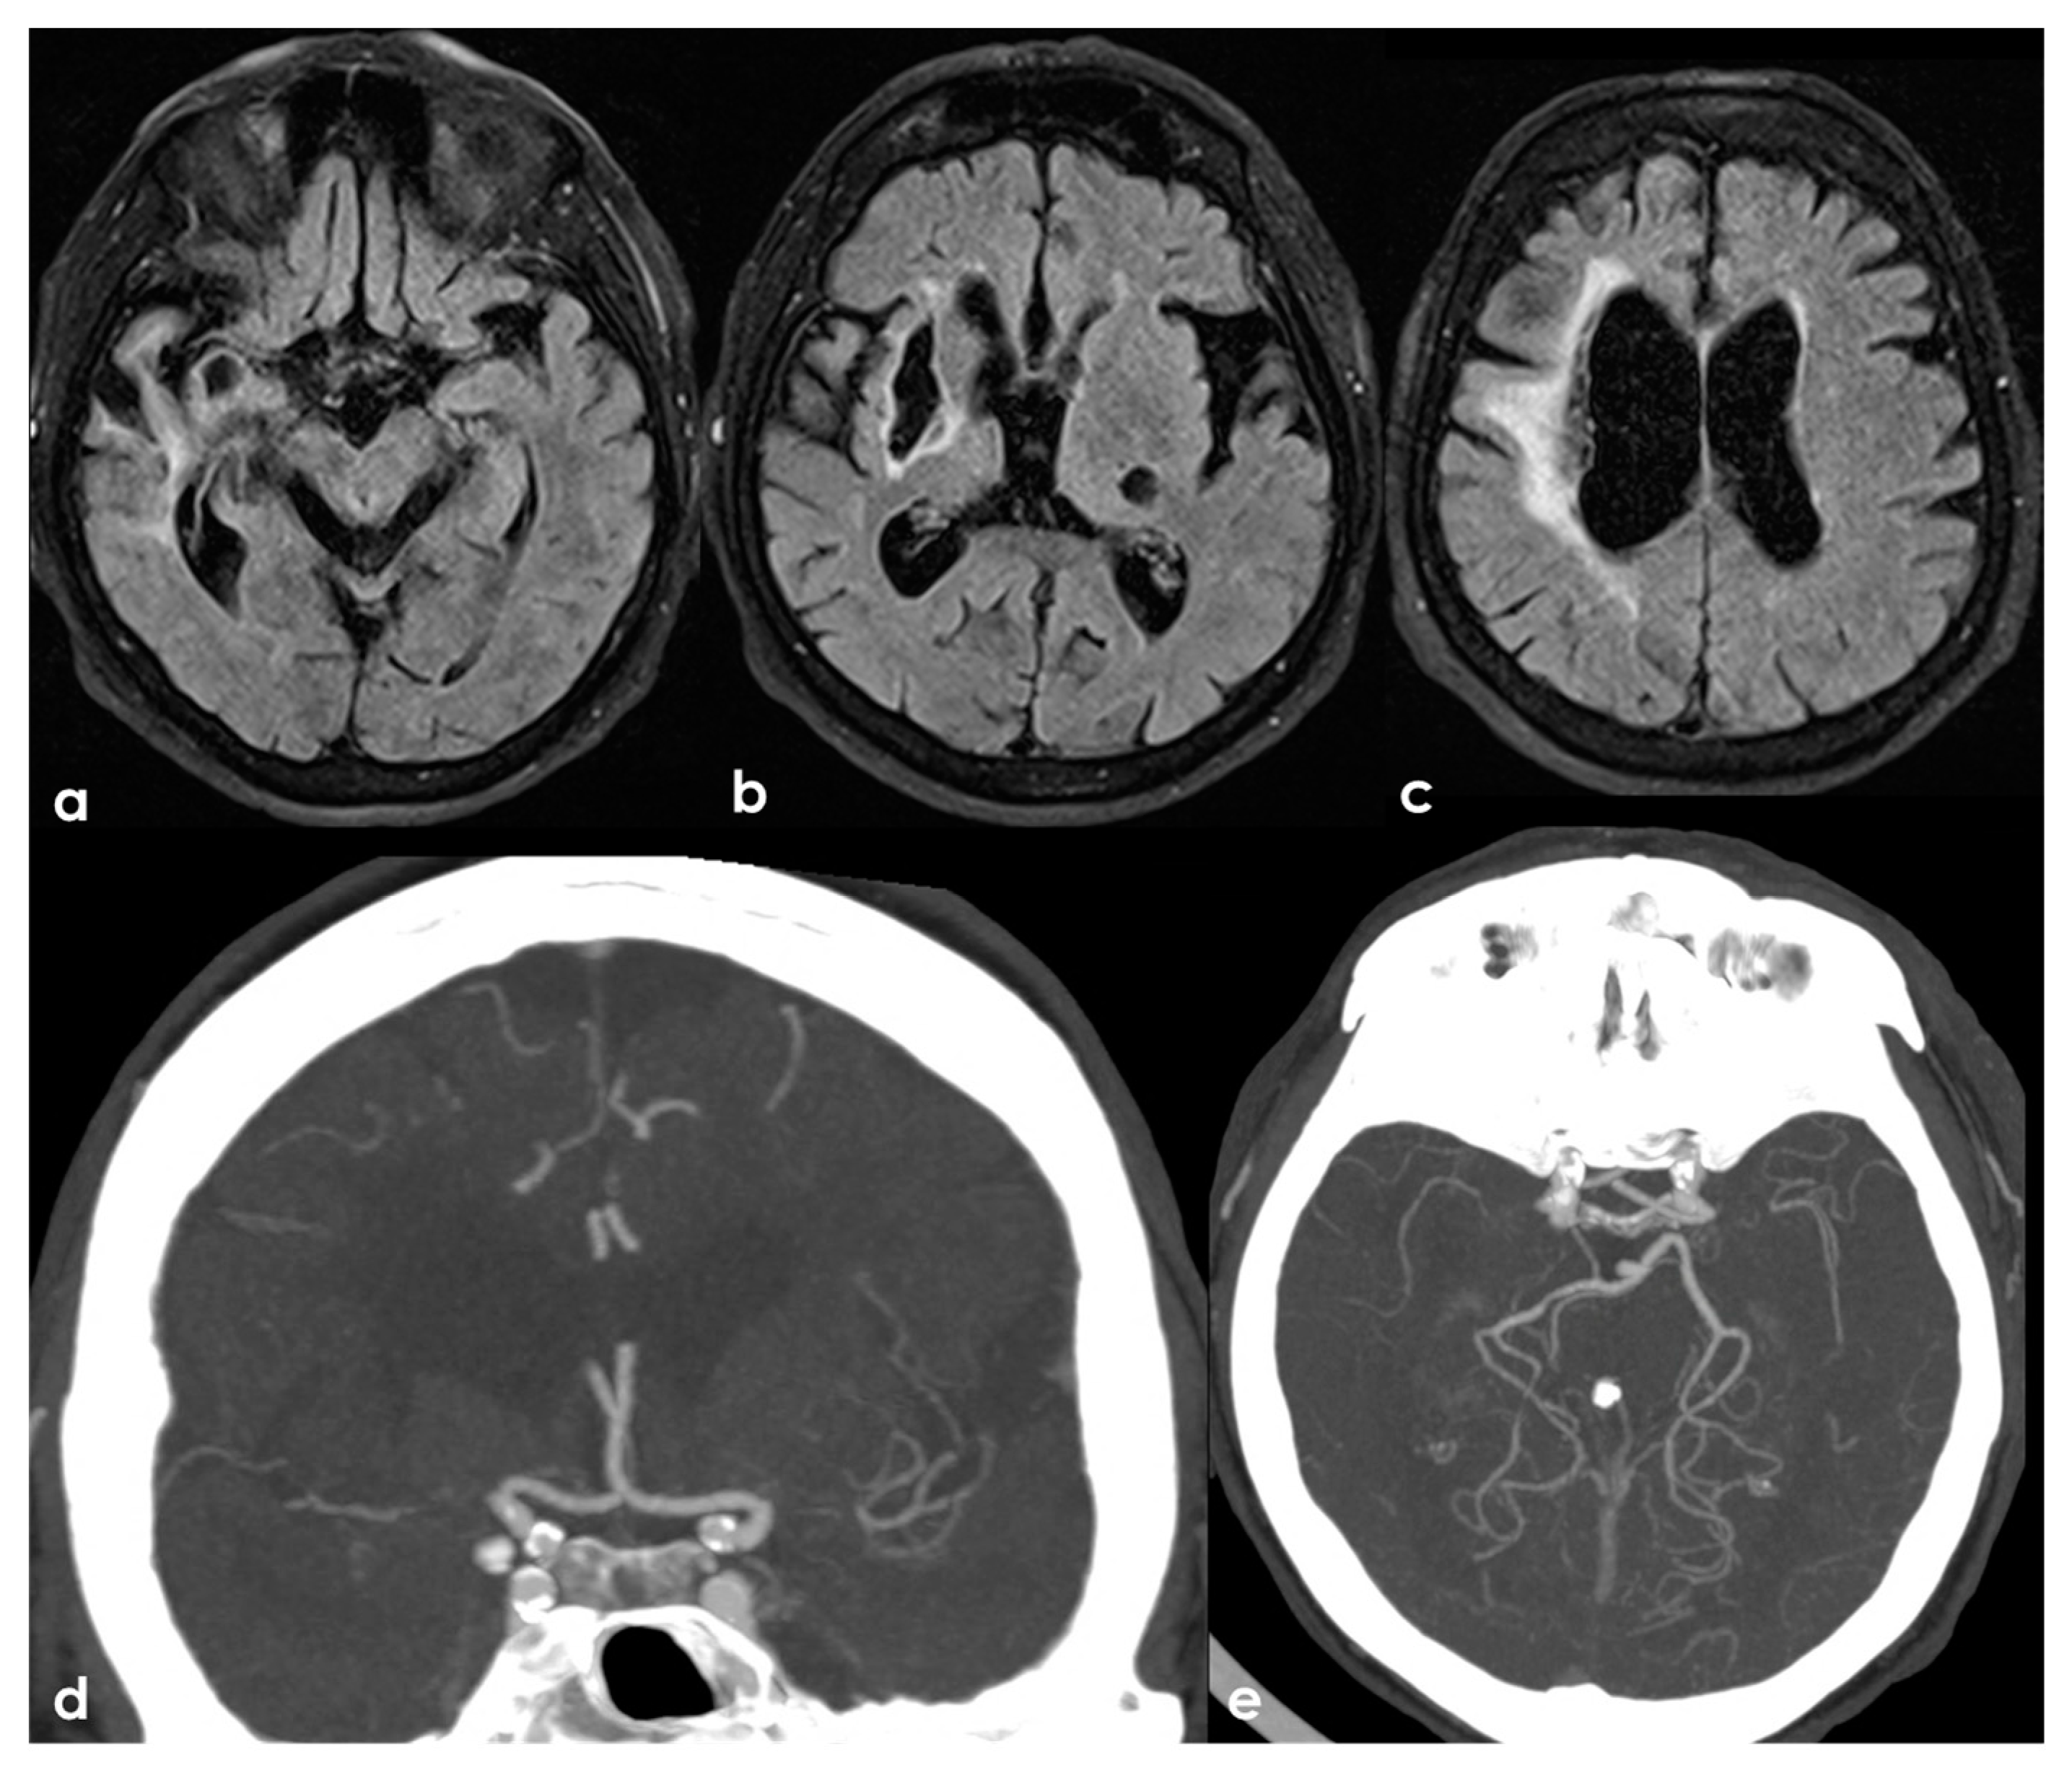

Figure 5.

An example of multifocal cerebellar ischemic lesions in a patient with APS (double positivity). Brain MRI (axial FLAIR in (a,b), coronal T2W sequence in (c) shows the poromalacic evolution of multiple ischemic lesions involving both cerebellar hemispheres (right ≥ left). No causes other than APS were identified in this patients.

Figure 6.

Brain MRI (axial FLAIR in panels (a–c) and the corresponding DWI slices in panels (d–f)) showing multifocal ischemic lesions in the left PCA territory with a patent PCA on MRA (panel (g)).

Figure 7.

Brain MRI (axial FLAIR in panels (a,b) and coronal T2W sequence in panels (c,d)) showing multiple cortico-subcortical ischemic lesions on both hemispheres and only few mildest SVD markers.